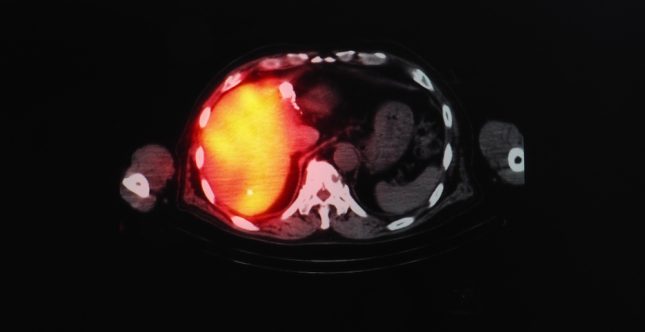

סרטן הכבד

האם Pembrolizumab יעילה כטיפול קו שני במטופלים עם סרטן הכבד?